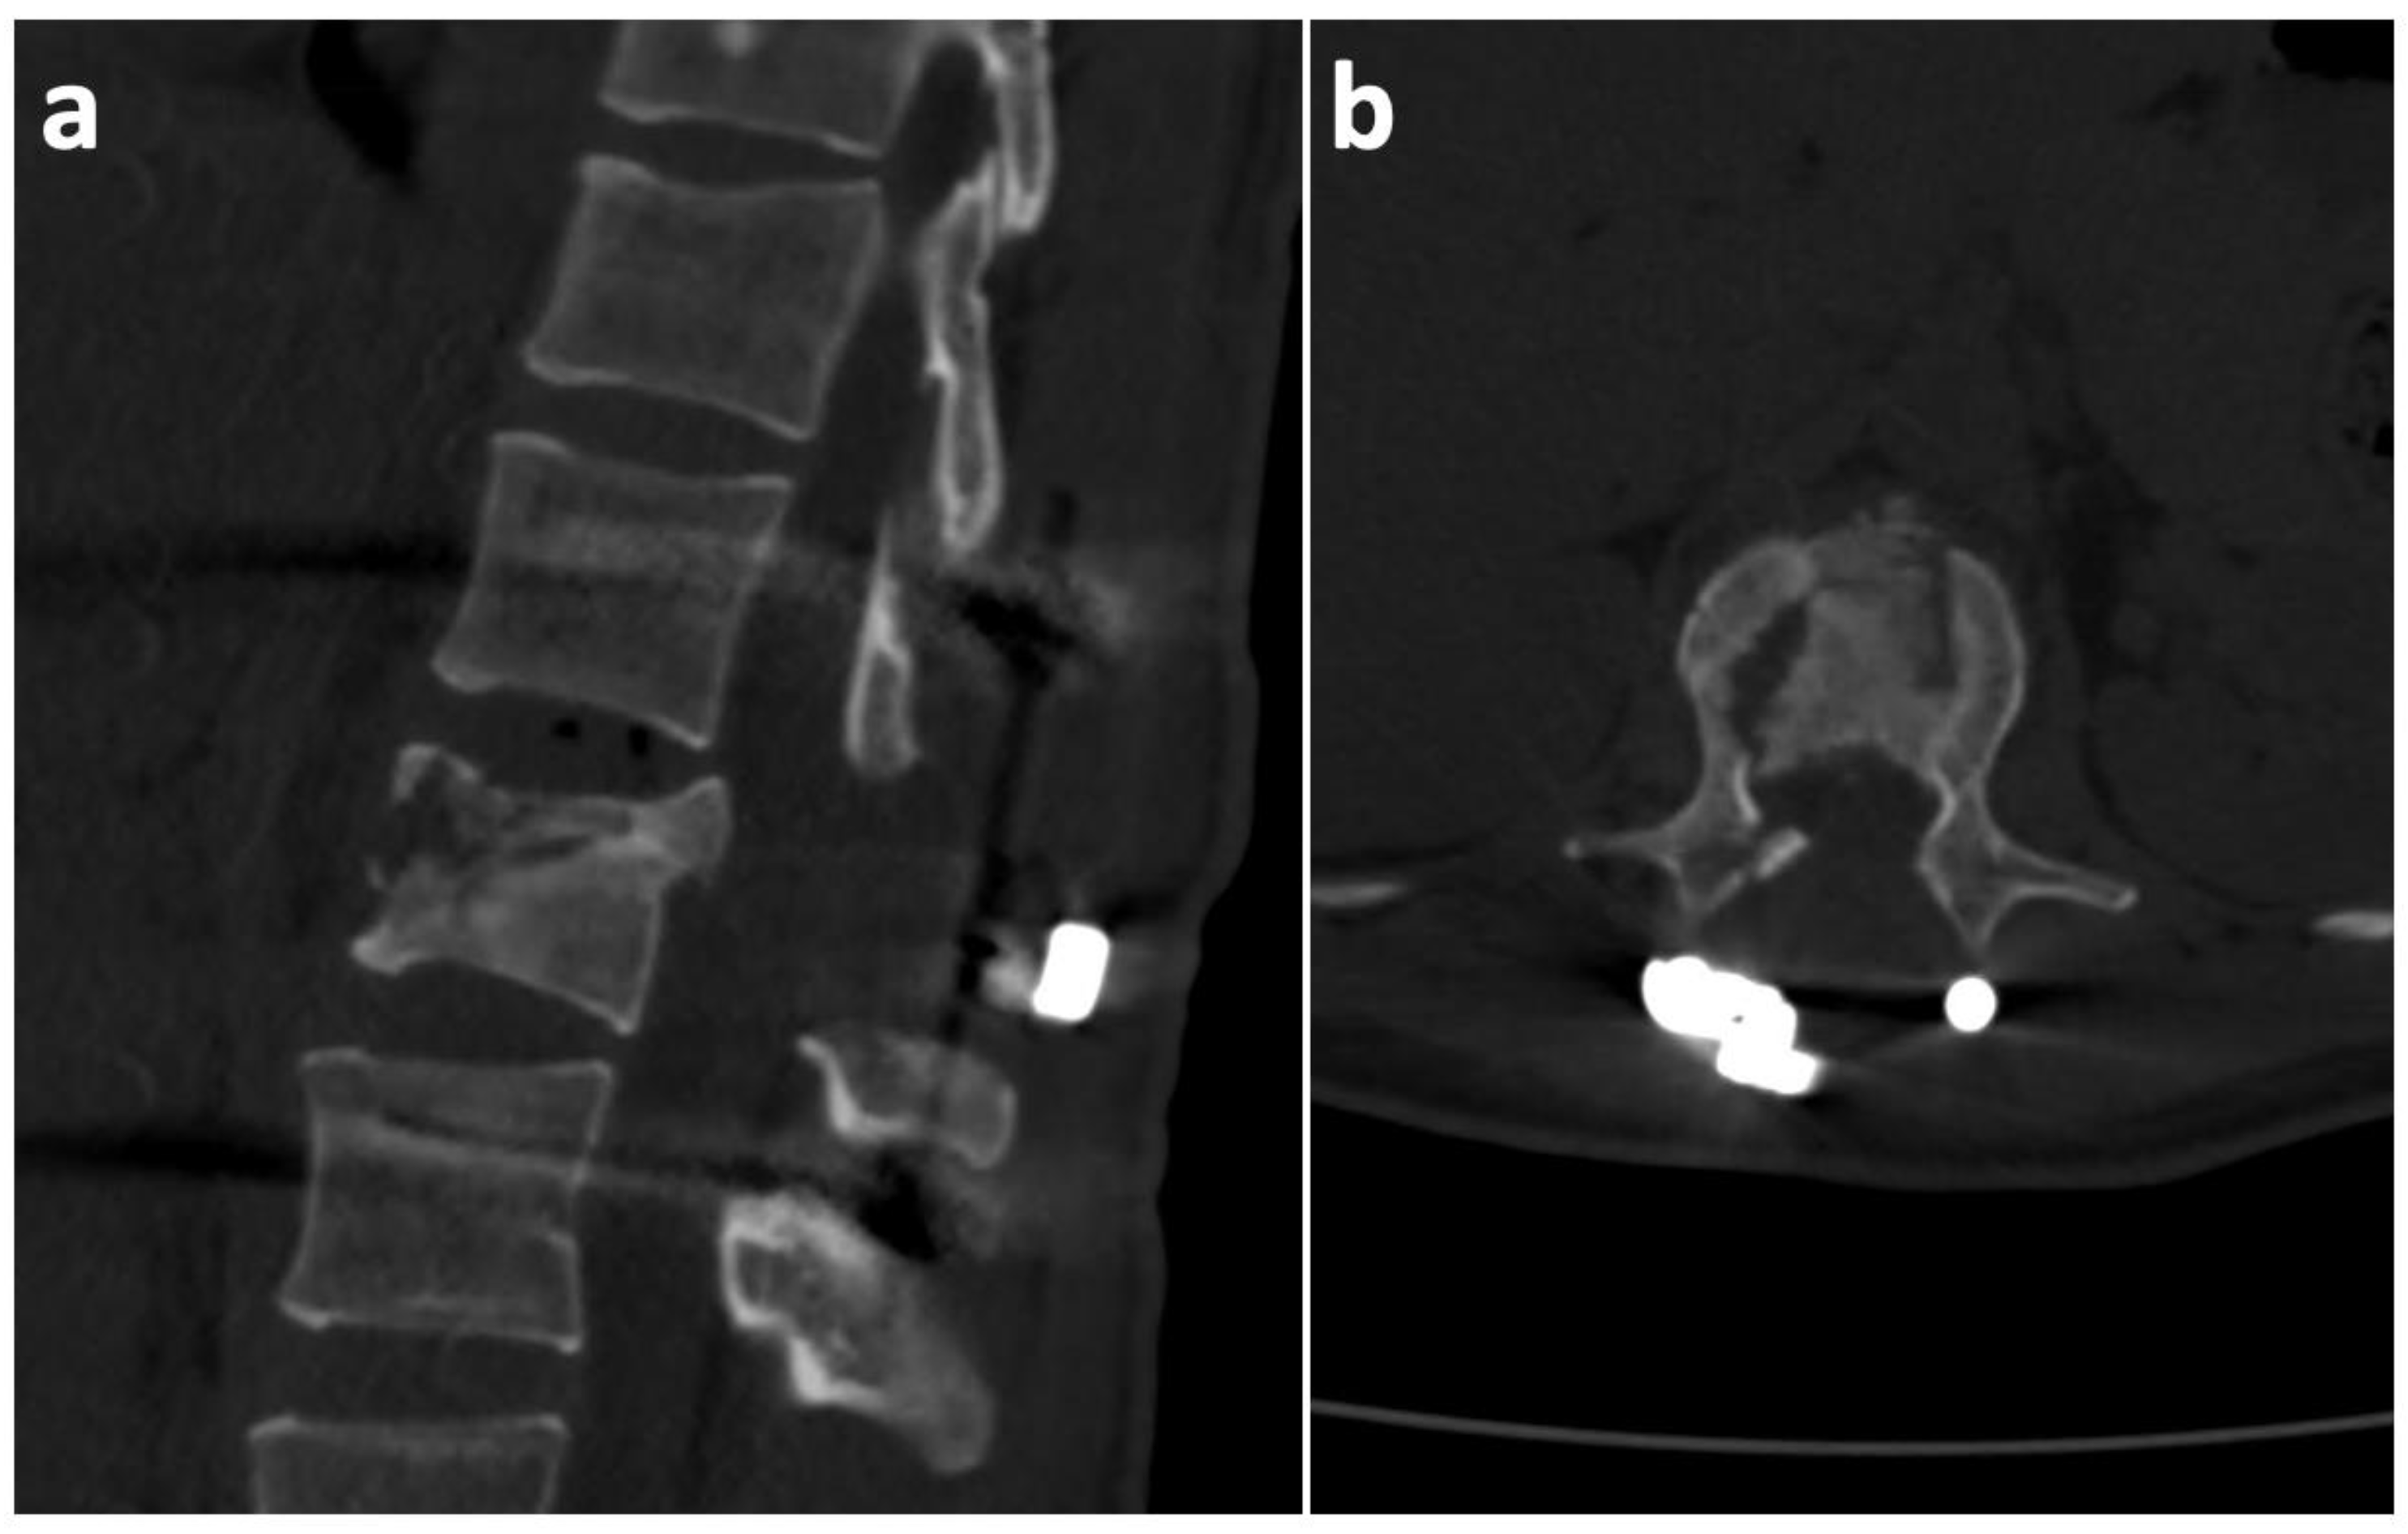

2. Case History